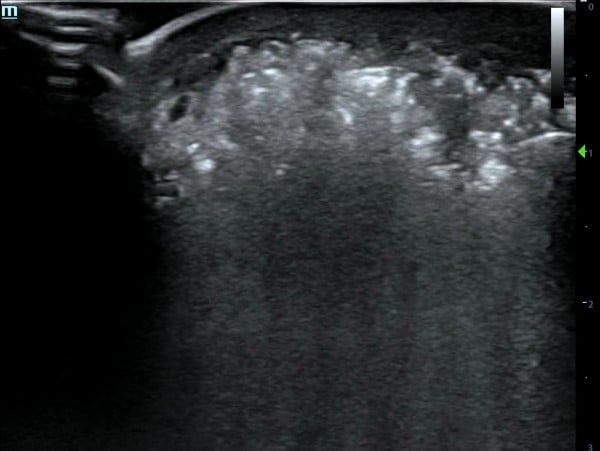

To further assess the extent of the wound, the emergency physician performs a point-of-care ultrasound (POCUS) to the lateral aspect of the right foot using the linear probe in the musculoskeletal (MSK) preset. Within the subcutaneous tissue, numerous hyperechoic foci are present with posterior dirty shadowing (Image 1). Additionally, an anechoic layer is visualized at the suprafascial layer (Image 2).

Image 1. Hyperechoic foci with posterior dirty shadowing.

To optimize the ultrasound settings, a linear probe should be used and set to the musculoskeletal (MSK) setting. Classic POCUS findings of NF include fascial thickening and subcutaneous tissue thickening. In gas-forming infections, the most specific finding is subcutaneous air, which appears as hyperechoic foci with posterior dirty shadowing. In contrast, in non-gas forming infections, the key finding is anechoic fluid tracking along the fascial plane, with fluid collections >4 mm considered significant.8-10